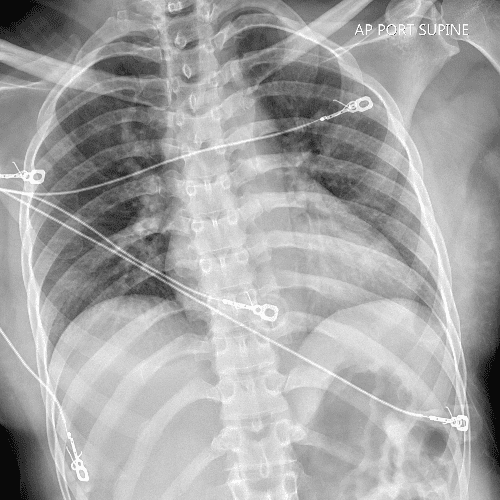

Practice Cases